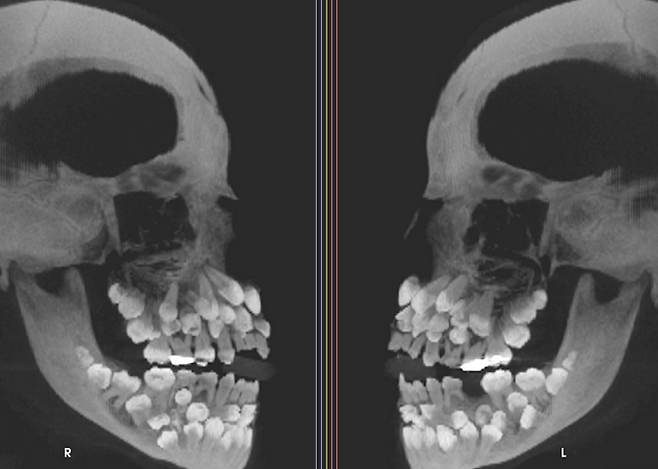

최근 VN익스프레스 등에 따르면 브라질에 사는 11세 소녀의 구강 엑스레이 결과 입 안에서 유치 18개와 영구치 32개, 과잉치 31개 등 총 81개 치아가 발견된 특이 사례가 미국 치과교정·악안면외과학회지에 보고됐다.

이 소녀는 위쪽 유치 1개를 뽑기 위해 병원을 찾아 엑스레이(X-ray)로 얼굴을 촬영했다가 사실을 알게 됐다.

일반적으로 영구치는 32개(사랑니 4개 포함)가 난다. 이보다 많은 치아가 있는 경우 '다발성 과잉치증(multiple hyperdontia)'로 진단한다. 과잉치증이라고 해도 보통 1~2개가 더 발견된다. 이번처럼 30개가 넘는 과잉치가 확인된 사례는 매우 드물다.